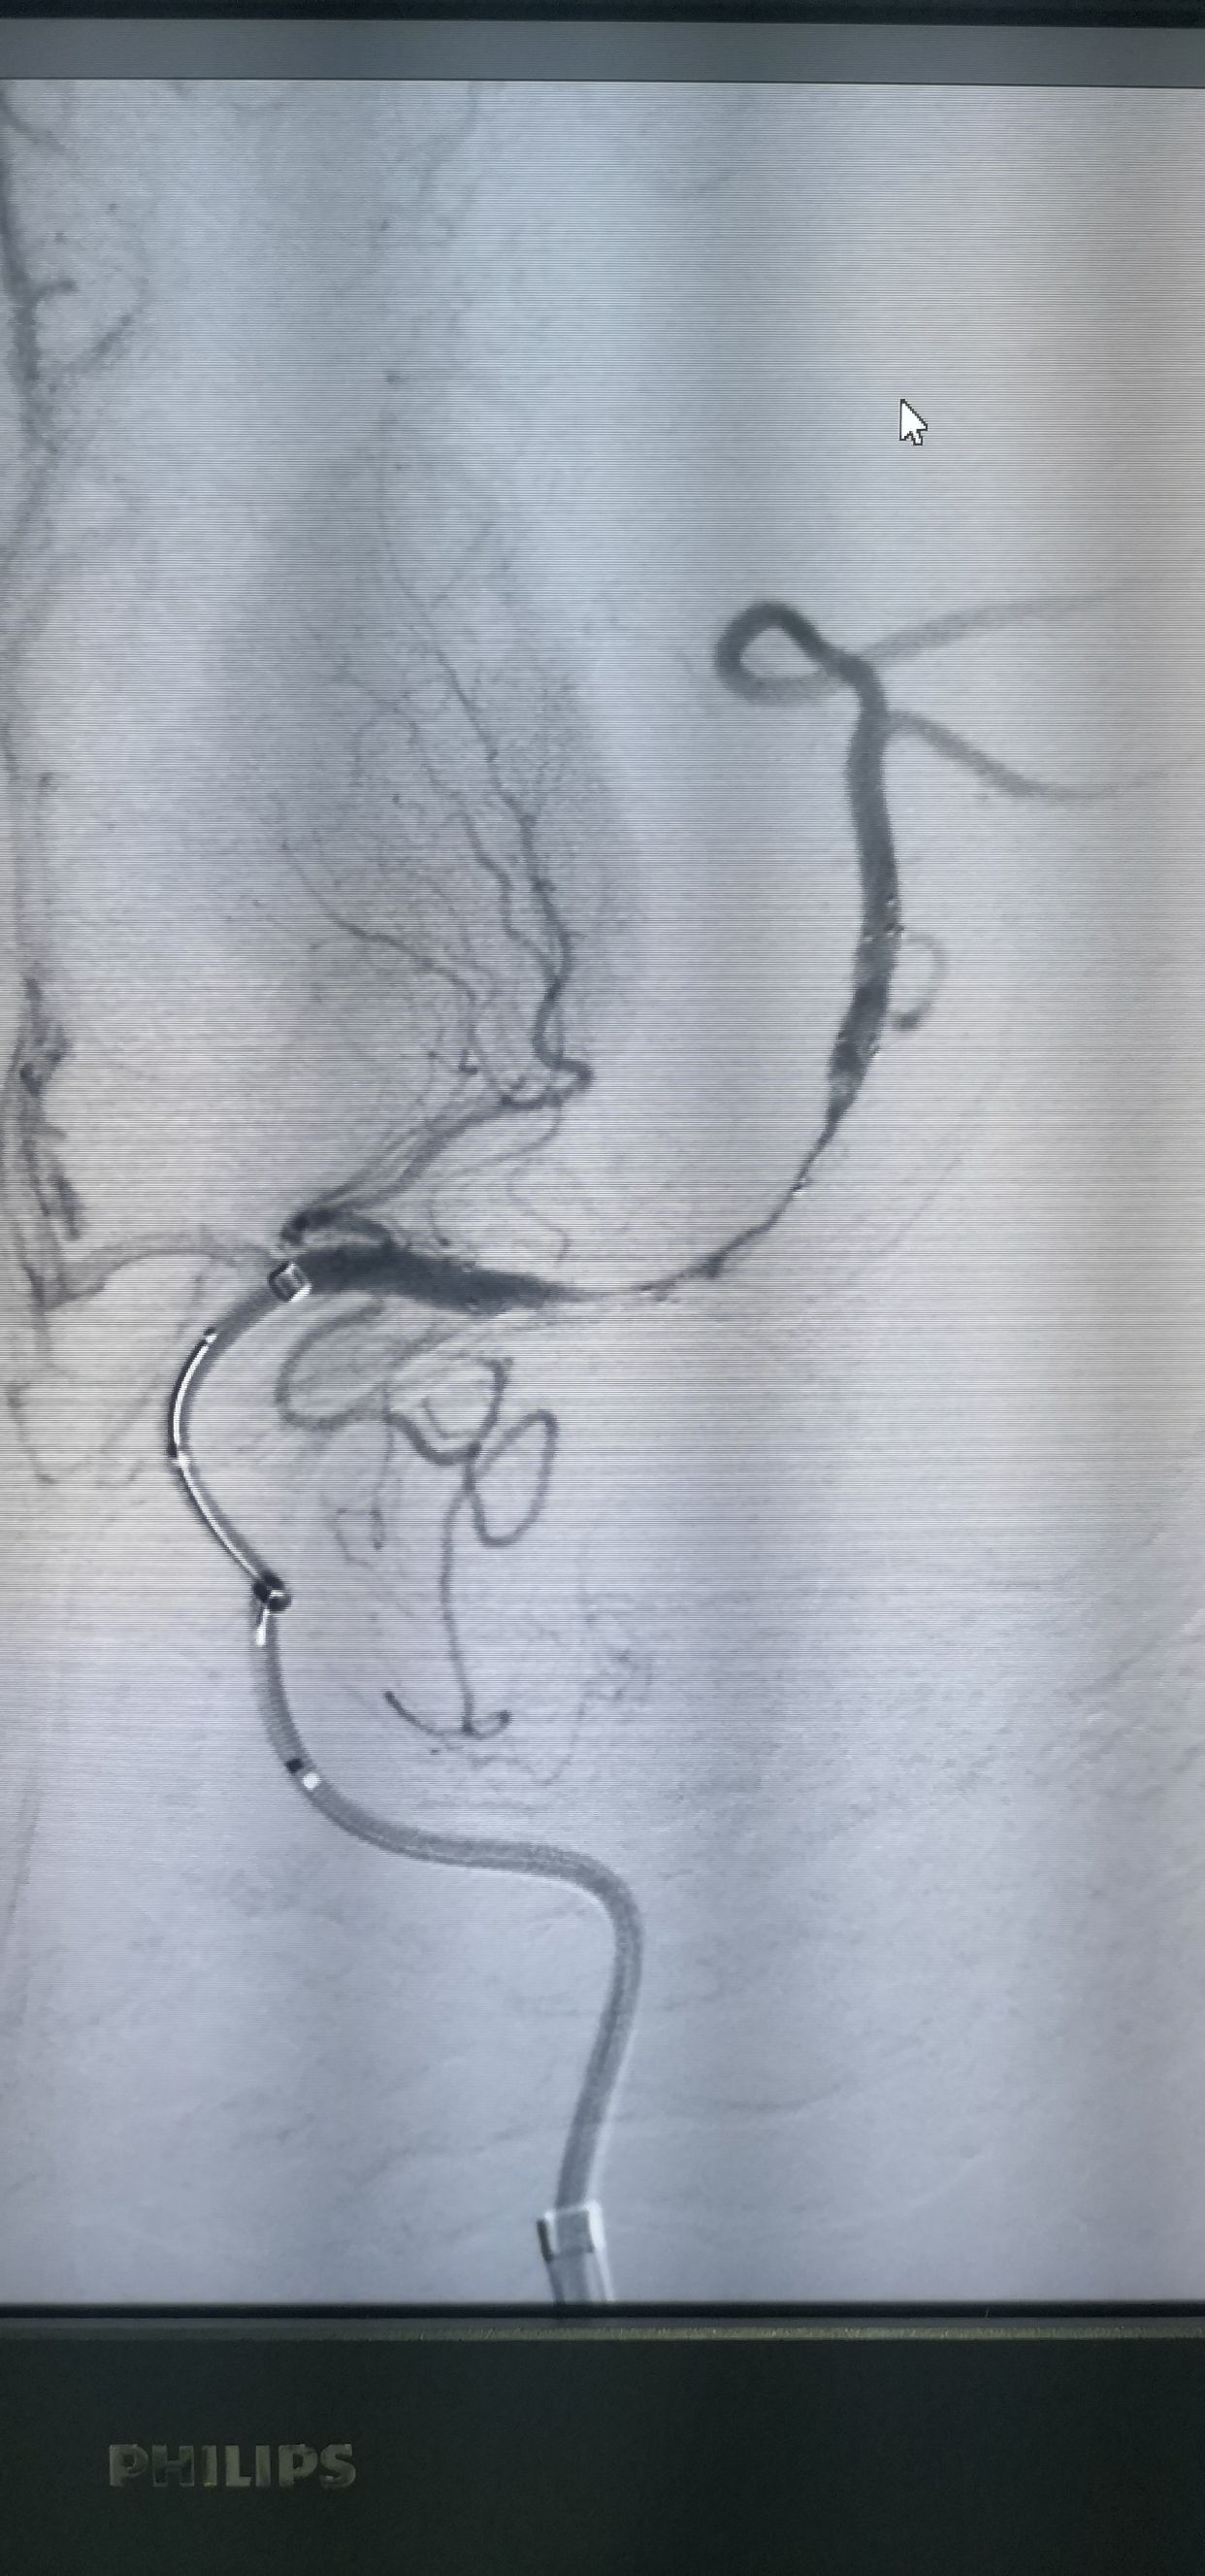

椎动脉造影,左侧软膜支有少量代偿

右侧大脑中动脉向左侧未见代偿

急性左侧大脑中动脉闭塞,考虑栓塞

侧位

navi到位

微导管到位造影,首过效应阴性

首过效应阴性

支架释放

释放支架后造影,提示有下干充盈缺损

支架配合抽吸导管取栓